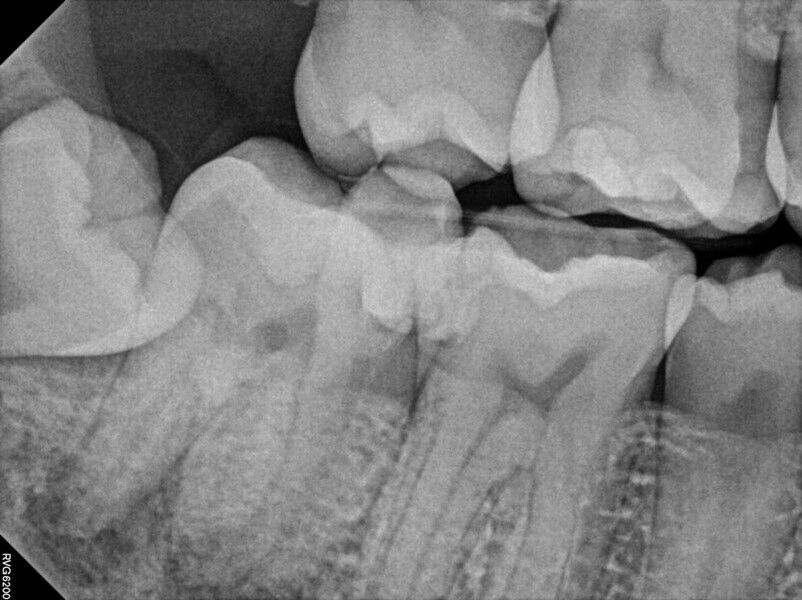

Fig. 14a: Case treated with Bassi Logic controlled memory nickel titanium files. Note the visualization of the third root on this lower molar and conservative canal preparation shape. (Courtesy of Dr. Alex Chan)

Fig. 14b: Case treated with Bassi Logic controlled memory nickel titanium files. Note the visualization of the third root on this lower molar and conservative canal preparation shape. (Courtesy of Dr. Alex Chan)